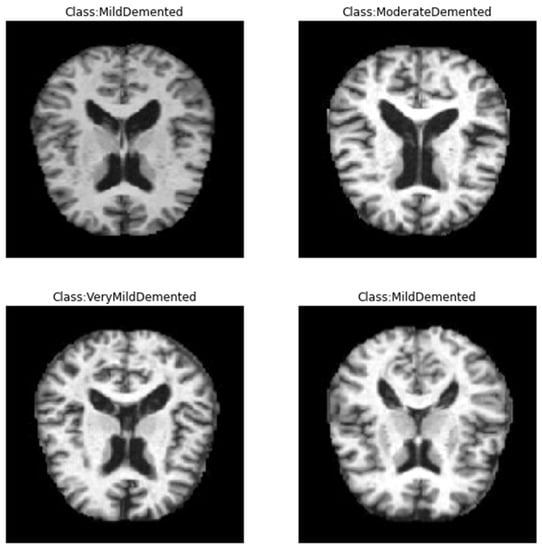

In this study, we employed the Alzheimer’s dataset [29], which is a hand-collected dataset consisting of MRI images that have been verified and labeled by experts. The data includes four different classes of images: Mild Demented, Moderate Demented, Non-Demented, and Very Mild Demented. These images can be used to train and test deep learning models aimed at accurately predicting the stage of AD. The dataset provides an opportunity for researchers and practitioners to develop algorithms that can accurately diagnose AD and aid in the development of effective treatments. With the growing global burden of AD, this dataset could play an important role in advancing our understanding of the disease and improving patient outcomes. The dataset is available on Kaggle and can be easily accessed, unlike other datasets, which are difficult to access. By making this dataset publicly available, the creators aim to encourage more research in the field and support the development of better algorithms for the diagnosis and treatment of AD. We employed this dataset as it is totally free, available with different classes, and small in size on a hard disk, unlike other common datasets in this field. Figure 1 shows samples of the dataset for the different classes. Table 2 shows the distribution of the records in the dataset, and Figure 2 shows the statistics of this dataset. Furthermore, a comparison between this dataset and other common datasets in this field is shown in Table 3.

Figure 1.

Sample of the data from Kaggle database [29].